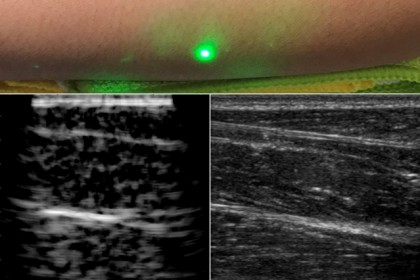

Oamenii de știință de la Massachusetts Institute of Technology au venit cu o alternativă la ecografia convențională. Noua ecografie cu laser folosește un sistem laser sigur pentru ochi și piele și oferă imagini de la distanță cu interiorul corpului unei persoane.

Noua tehnologie nu necesită contact cu corpul unui pacient. Un laser generează unde sonore de la distanță care trec prin corp. Un al doilea laser detectează de la distanță undele reflectate, pe care cercetătorii le transformă apoi într-o imagine similară cu ecografia convențională.

foto: MIT News (Image courtesy of the researchers)